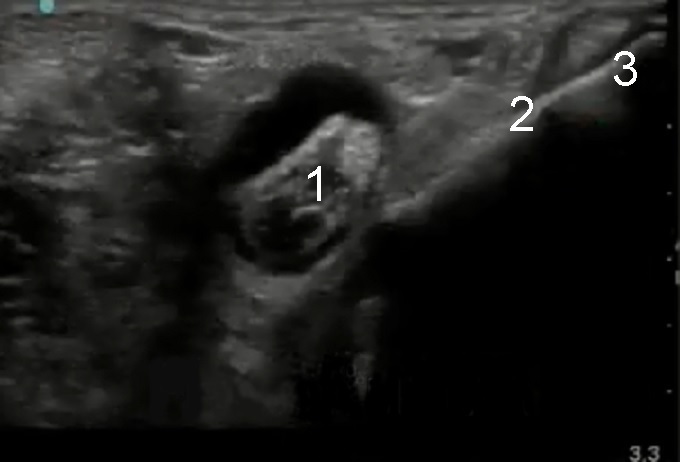

1. Flexor Hallucis Longus

2. Flexor Digitorum Longus

3. Posterior Tibialis Tendon